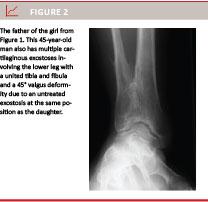

The MCE patients’ clinical symptoms are localised pain, cosmetic disturbances, abnormal osseous growth and deformities of joints [1-16]. The latter can result in low stature, discrepancy of leg length, valgus deformities in the knee and ankle, asymmetric pelvine and pectoral regions and bending of the radius bone resulting in subluxation of carpus [8]. Treatment is surgical resection since this prevents or reduces the progression of deformities and functional impairment caused by an OC (Figure 3). Otherwise, treatment is not recommended in asymptomatic cases [14].